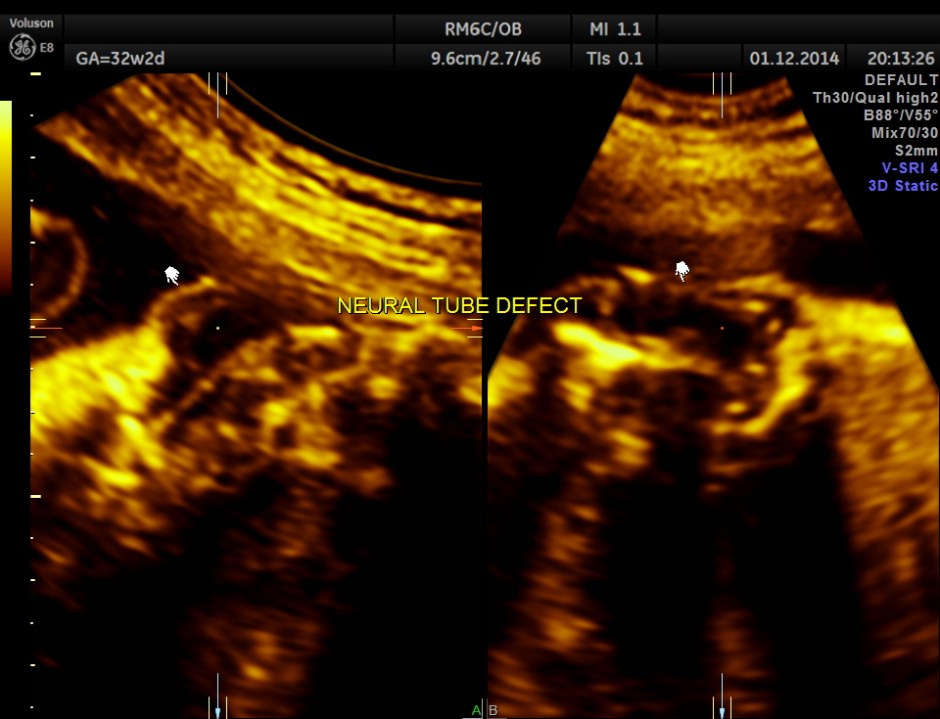

3D view of the same.

Careful examination revealed a neural tube defect with meningo myelocele at the lumbo sacral level.